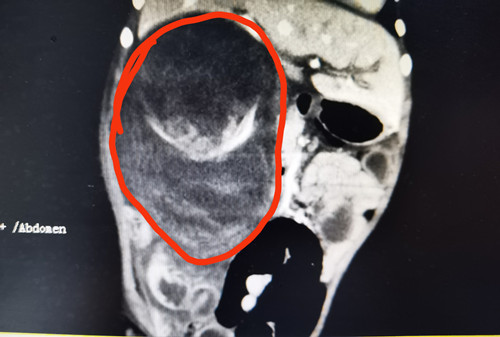

检查结果显示巨大肿瘤。

湖南耒阳2岁的男童琦琦(化名)半个月前被家人发现肚子硬、尿片上有淡红色血迹,还以为是上火、积食,用了几种降火药,奶奶还找来了“土方”,都不见效果,辗转来到湖南省人民医院儿童血液肿瘤科,医生发现琦琦右肾有一个11.5*10.1cm的巨大肿瘤,而且已经破裂出血,危及生命,立即为其安排了手术,手术切除了肿瘤和右侧肾脏,术后病理诊断为肾母细胞瘤,目前琦琦恢复良好,准备出院。